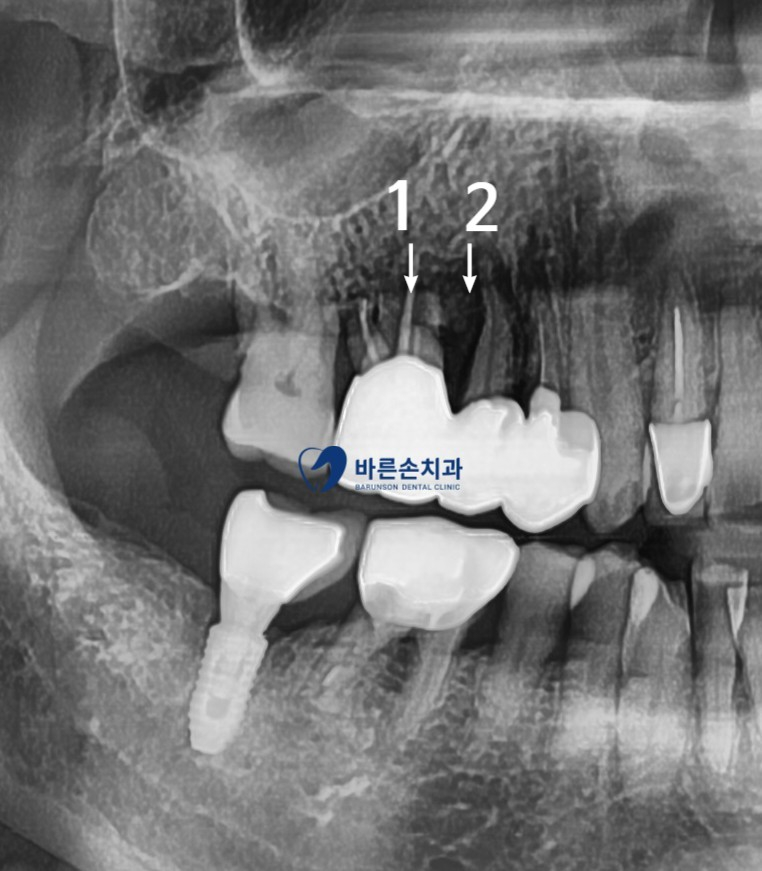

파노라마 판독 결과

1번 치아 뿌리에 파절이 보이고

2번 치아에는 치조골 손상이 보이네요

통증의 원인된 치아 발치와 함께 기존에 있던 염증을 깨끗히 제거 합니다

염증으로 인해 치조골 손상도가 높은 케이스라 상악동 거상과 치조골 이식을 동반하였습니다

이로 인해 알맞은 위치에 임플란트가 잘 고정되어져있는게 보이네요^^